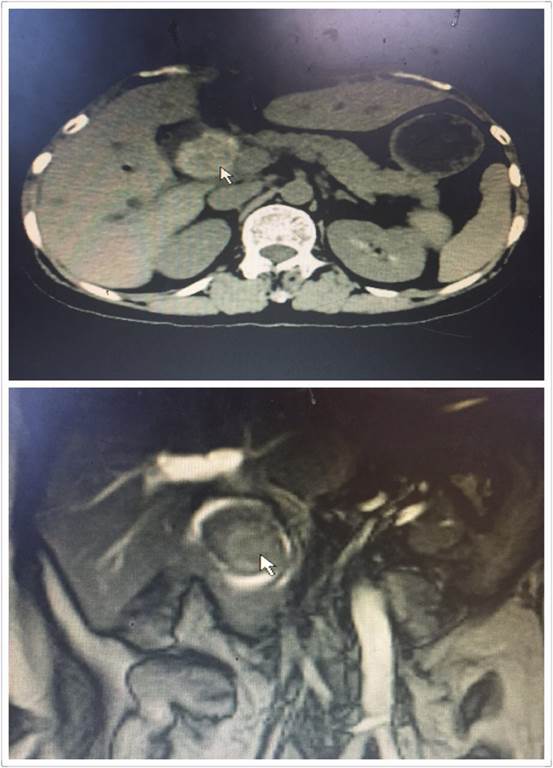

腹腔鏡手術(shù)雖好,但是對于有腹部多次手術(shù)史、腹腔廣泛粘連的患者來說,由于腹腔解剖結(jié)構(gòu)改變,腹腔鏡手術(shù)倒變成了雷區(qū)。近日,肝膽外科收住了一位老年患者,進(jìn)院時已出現(xiàn)了腹痛、發(fā)熱、黃疸。進(jìn)一步檢查后顯示,患者膽總管結(jié)石阻塞膽管,膽道擴張,肝功能差,急需手術(shù)治療(見圖1)。然而這位患者似乎有些“命途多舛”,在這之前她就曾因膽管結(jié)石、腸梗阻在外院作了三次大手術(shù),所以腹部留下了整整長約30CM的手術(shù)疤痕(見圖2)。外院的醫(yī)生了解到該情況后建議直接“開刀”,患者通過打聽得知我院腹腔鏡技術(shù)精湛,遂慕名而來。

圖1